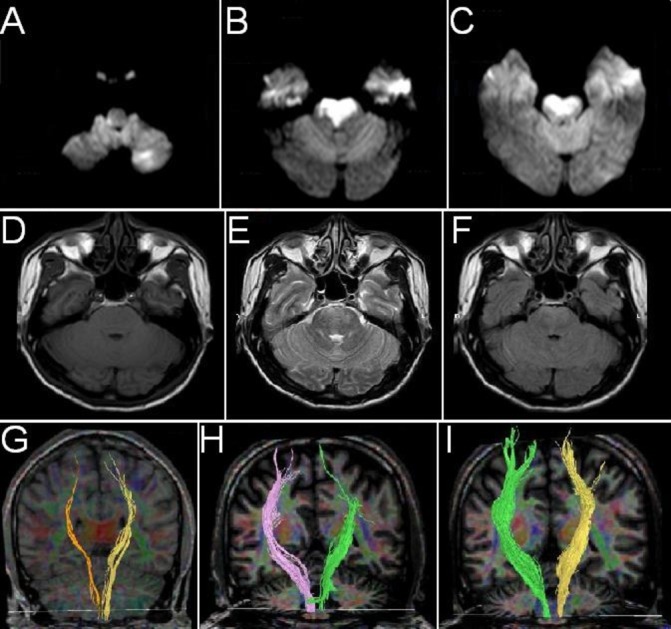

Figure 1.

MRI revealed acute ischaemic lesions in the right dorsolateral medulla, the left cerebellum and the pontine base (A–C). No intracranial haemorrhage was detected (D–F). Injured corticospinal tracts at admission (G) recovered to normal level at 1-month (H) and 3-month (I) follow-up. FA values of bilateral pontine also increased during the follow-up (FA at admission, 1 month and 3 months: Left side: 0.421, 0.578, 0.525; Right side: 0.396, 0.550, 0.583). FA, fractional anisotrophy.

Neurological deficits of the patient resolved rapidly within 2 weeks and NIHSS score at 1 month follow-up was only 2. The injured CST, visualised by diffusion tensor imaging (DTI) using FiberTrak software (Philips Healthcare, Amsterdam, The Netherlands), recovered to normal level during a 3-month follow-up (figure 1G–I). Repeated cerebral angiography demonstrated that the stent was patent along its whole length and there was no sign of stent deformity or in-stent thrombosis over a follow-up of 1 year (figure 2E–H).